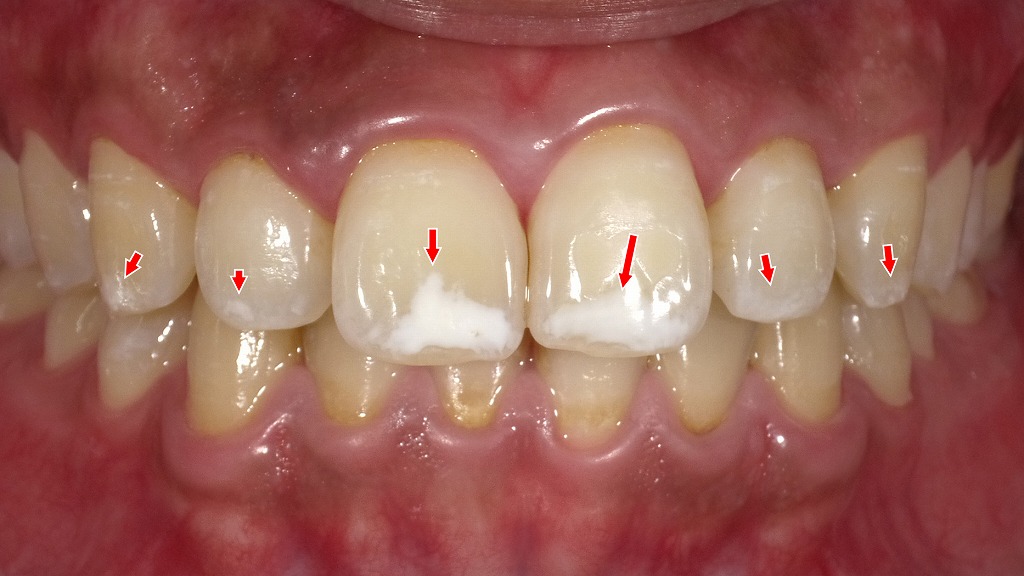

1枚目の画像:術前

1枚目の画像では、上顎前歯(特に中央の2本)に白く不透明な部分が見られます。これはエナメル質形成不全によるホワイトスポットです。歯が作られる発育期に、エナメル質のミネラルが十分に沈着せず、部分的に構造が弱くなった結果、光の反射が異なり白く濁って見える状態です。むし歯ではなく、表面は滑らかで痛みもありませんが、審美的に気になる方が多い症状です。